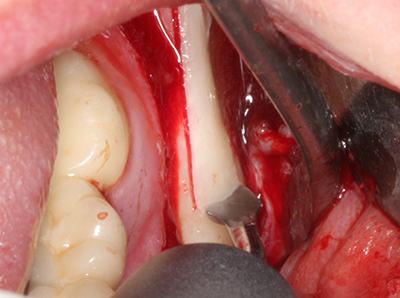

Bone tissue is not simply a mineral structure but also contains a substantial proportion of collagen fibres. This means it not only has good compressive strength but also a degree of flexibility, which can be taken advantage of when performing bone augmentations. In the classical expansion procedure using bone splitting, the atrophied alveolar ridge is split longitudinally and carefully expanded after reaching an adequate osteotomy depth (Fig. 13-16), ideally without substantial removal of the periosteum (Brugnami, Caiazzo et al. 2014, Stricker, Fleiner et al. 2014). Screw and plate systems with increasing expansion distance have proven effective in separating the two bone lamellae while remaining below the fracture threshold. In general, residual bone widths of at least 3–4 mm are required (Chiapasco, Zaniboni et al. 2006) to guarantee adequate flexibility and sufficient bone coverage of the future implants. If necessary, a vertical relief osteotomy on one or both sides can improve flexibility. A combination with additional augmentation techniques, particularly on the buccal side, has been described as an alternative to the classical technique.

The splitting procedure is particularly atraumatic and there is no significant loss of dimension when using piezosaws, and there are no significant differences between implants in split jaws and implants in an alveolar ridge without a bone deficit (Chiapasco, Zaniboni et al. 2006, Danza, Guidi et al. 2009). However, sufficient continuous irrigation is essential, particularly with locally restricted and deep splitting to prevent thermal stress in the apical osteotomy regions.